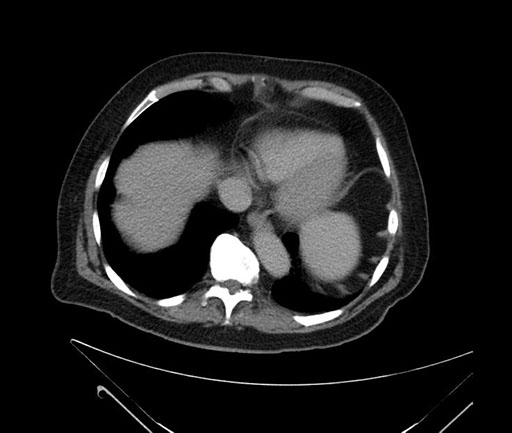

Axial - 3 months prior